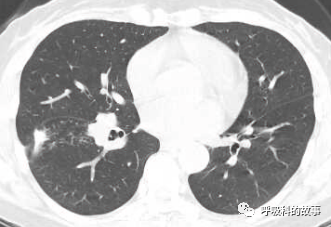

1個月前,黃女士來到了杭州市第一人民醫院呼吸科,找到我看病,我給她複查了肺部CT,如下:

初一看,好像就是普通的肺炎,可是為什麼相隔兩個月在同一部位反覆發生呢?另外,右下葉肺門較左側明顯增大,感覺到管腔似乎也不是那麼清爽,於是我繼續開啟縱隔窗繼續檢視影像情況。

這一看嚇我一跳,患者右下葉支氣管腔內有高密度影,這讓我首先想到的就是支氣管異物堵塞管腔,從而引起阻塞性肺炎。於是我在認真檢視後,嚴肅地對患者說要住院。黃女士可能一來工作繁忙,二來對我的診斷可能表示懷疑,因為她記憶裡沒有誤吸的事件發生,三來以前的CT報告也沒有提示支氣管異物,於是要求繼續口服藥物治療。